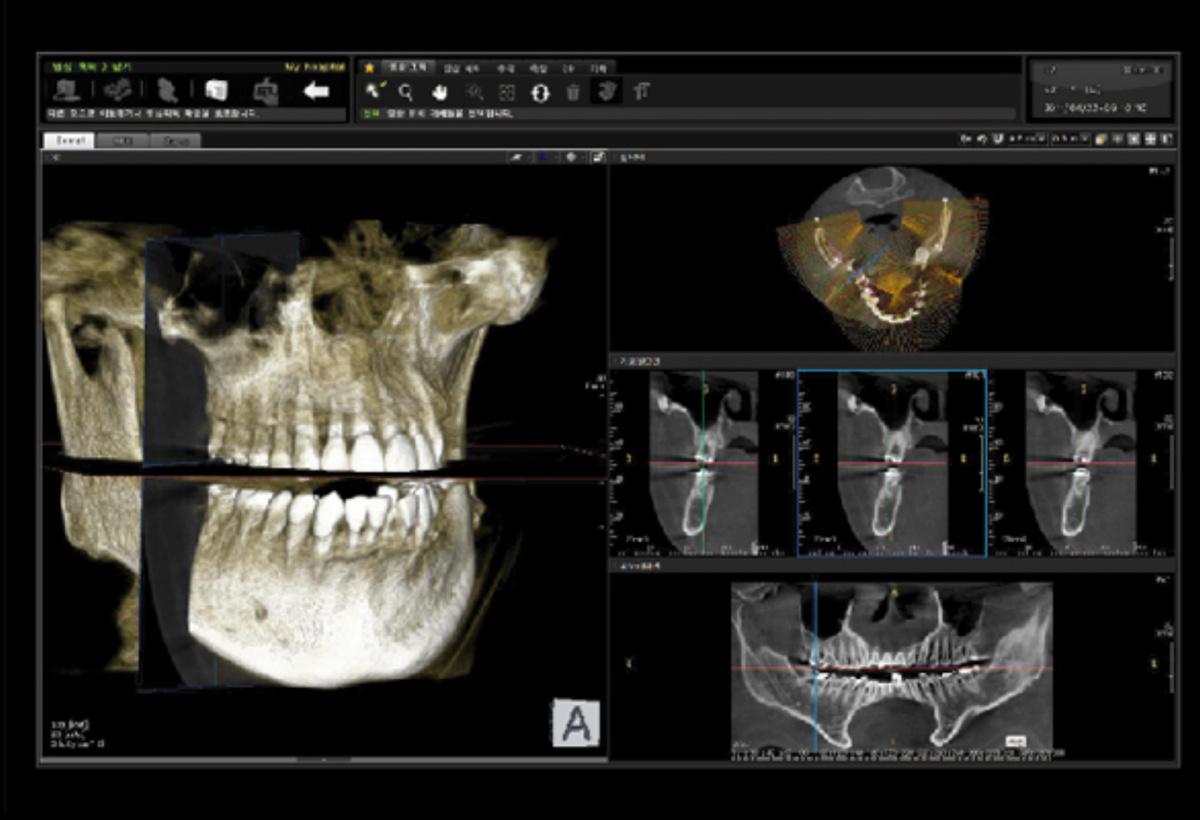

Немаловажным, а может главным вопросом, является универсальность программы-просмотровщика, в которой будут работать врачи-стоматологи. У Papaya 3D есть два варианта программ: Triana и OnDemand3D. Оба просмотровщика обладают схожим интерфейсом и имеют самые важные опции, а именно:

• режим MPR (многоплоскостная реконструкция). Именно здесь выстраивается интересующий участок челюсти или зуба для анализа.

• панорамный реформат. Возможность постройки классической и сегментарной панорамы позволяет продемонстрировать план лечения пациенту, а также оценить расположение анатомических структур на боковых кросс-секциях.

• модуль дентальной имплантации. Возможность виртуальной установки дентального имплантата с анализом окружающей костной ткани. В библиотеке представлен широкий спектр имплантологических систем с индивидуальной прорисовкой имплантата.

• выделение нижнечелюстного канала позволяет продемонстрировать расположение важного анатомического образования и определить зону безопасности при проведении лечения.

• функции плотности, линейных измерений и угла – необходимы для получения полноценной информации для последующего лечения.

• 3D режим – показывает трехмерную модель челюсти с целью определения аномалий, деформация, а также визуализации виртуальных имплантатов.

triana3.jpg triana4.jpg triana5.jpg

OnDemand3D (1).jpg OnDemand3D (2).jpg OnDemand3D 1.jpg

Таким образом обе программы являются простыми в пользовании, но обладающими обширным спектром возможностей для диагностики любыми специалистами-стоматологами. В данные программы происходит загрузка классических файлов DICOM 3.0, которые являются общепринятым форматом записи данных пациента. Это важный момент, так как позволяют врачу, имеющему полную версию программы загружать даже сторонние исследования и просматривать их в этих программах. Простота в освоении этих программ позволяет даже специалисту, не работающему раннее с этими программами, быстро адаптироваться и получить качественную информацию. Возможность выгрузки STL-файла дополнительно создает возможность интегрировать данные с цифровым ортопедическим протоколом.